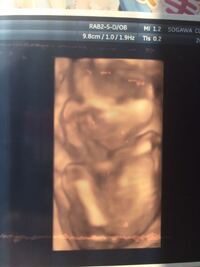

妊娠19週目 19w1d 6d のエコー写真とエピソード 妊娠5ヶ月 Cozre コズレ 子育てマガジン

この動きは、いったい何をしてる? 赤ちゃんの動きに集中してみると、胎動もいろいろな種類がいっぱい。今回はママたちが感じるよくある動きについて、お腹のなかの赤ちゃんの様子を調べて、想像してみました。 「ニョロ~ニョロ~」 あれ?妊娠19週はどんな様子 ママは胎動ない 感じない 赤ちゃん何してる Babydot ベイビードット 妊娠19週 胎児と母体の症状で知っておきたいこと ニンアカ 妊娠19週目 19w1d 6d のエコー写真とエピソード 妊娠5ヶ月 Cozre コズレ 子育てマガジン